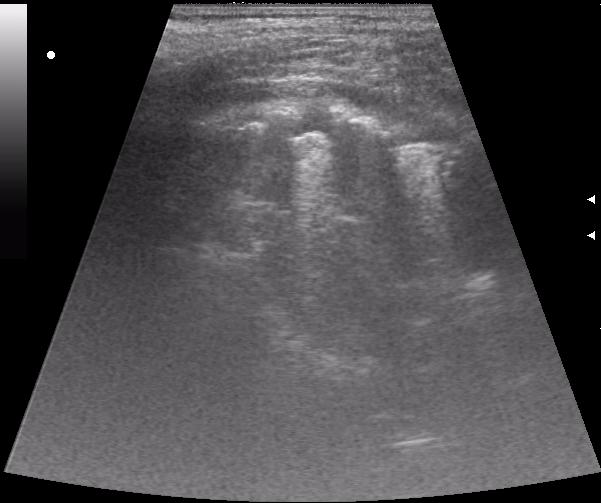

до операции